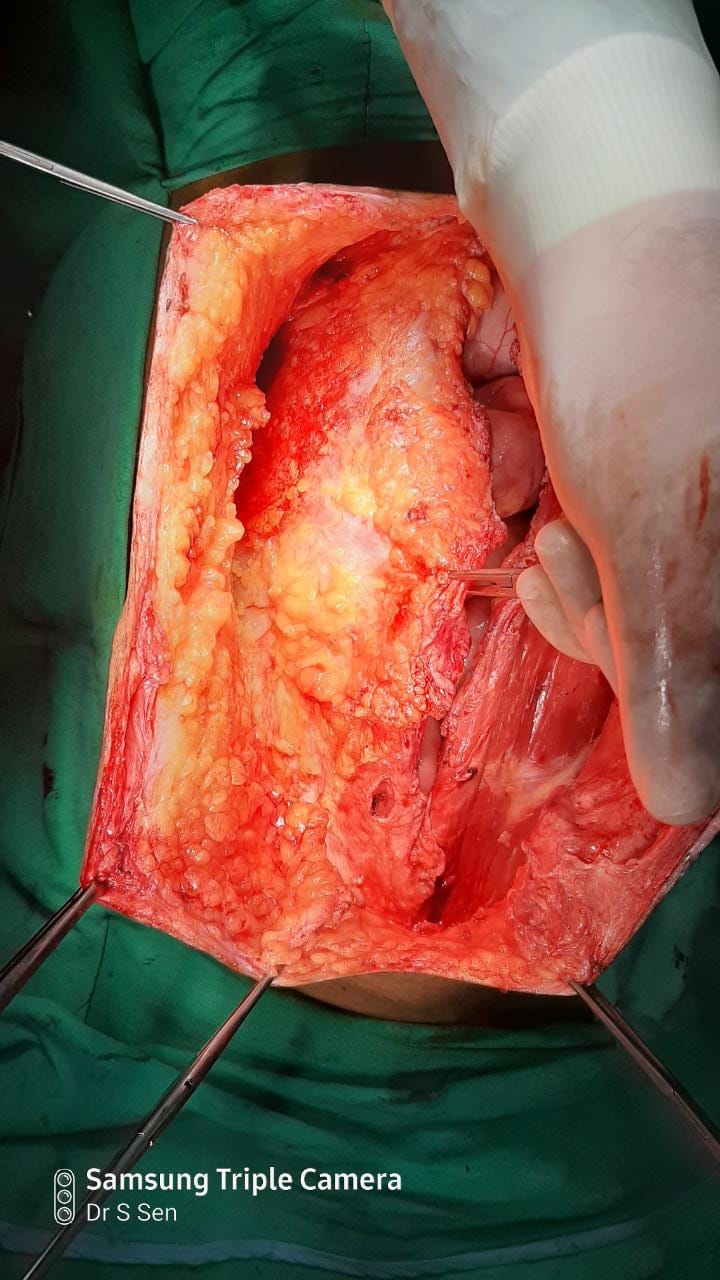

A Young lady who was a small kid...when her mother was operated for a Complex Gastrointestinal condition almost 14 years back by Dr Suddhasattwa Sen suddenly came in with severe blood loss from Gastrointestinal tract with a loss of almost 2 to 3 litres of blood with Shock with fainting . Further stabilisation was done and then extensive investigation revealed not only Piles and GI Ulcers but also SRUS Bleeding ulcers in rectum. A condition called Solitary Rectal Ulcer Syndrome ( a complex and difficult to cure anorectal problem ) . Her hemoglobin dropped to below 7 gm% She finally underwent surgery after 5 days and left home after 2 days post op without any further bleed or problems .